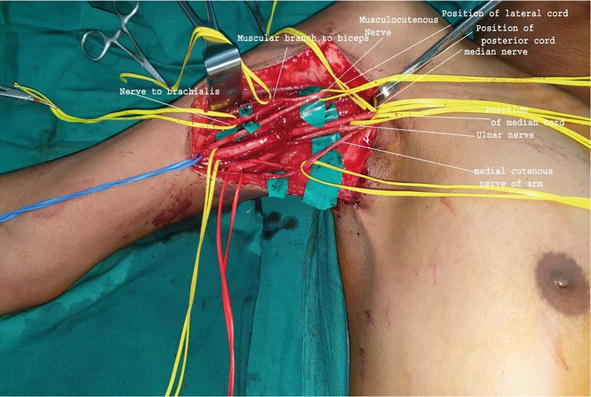

Plexus surgery involves advanced microsurgical techniques such as nerve repair, nerve grafting, and nerve transfer to restore nerve function. Early treatment and expert surgical care can significantly improve recovery and help patients regain strength and mobility.